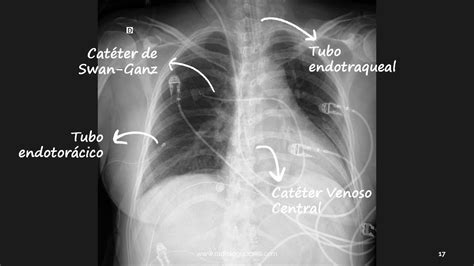

Procedimiento de Intubación

El tamaño del tubo y la profundidad de la intubación se seleccionan de acuerdo con el peso y la edad gestacional del bebé. Se ha estudiado la longitud entre la nariz y el trago (distancia desde la base del tabique nasal hasta el trago) más 1 cm como alternativa a la edad gestacional y el peso para determinar la profundidad de colocación del tubo endotraqueal. Muchos tubos endotraqueales tienen marcas de inserción que se colocan al nivel de las cuerdas vocales para guiar la colocación inicial.

Inmediatamente después de la intubación, los médicos deben auscultar el murmullo vesicular bilateral y simétrico. La intubación selectiva del bronquio principal derecho con disminución del murmullo vesicular del lado izquierdo es común si el tubo se inserta demasiado profundamente.

La intubación traqueal debe confirmarse mediante la prueba de CO2 exhalado utilizando un detector colorimétrico. Una prueba positiva, en la que el indicador colorimétrico cambia de púrpura/azul a amarillo, confirma la intubación traqueal. Una prueba negativa se debe más comúnmente a la intubación esofágica, pero puede ocurrir cuando la ventilación es insuficiente o el gasto cardíaco es muy bajo. Un color amarillo fijo puede deberse a la contaminación directa con adrenalina o puede indicar que el dispositivo está defectuoso.

La profundidad apropiada del tubo endotraqueal permite que la punta del tubo se encuentre en la radiografía de tórax en el punto medio entre las clavículas y la carina, lo que coincide más o menos con el nivel vertebral T1.